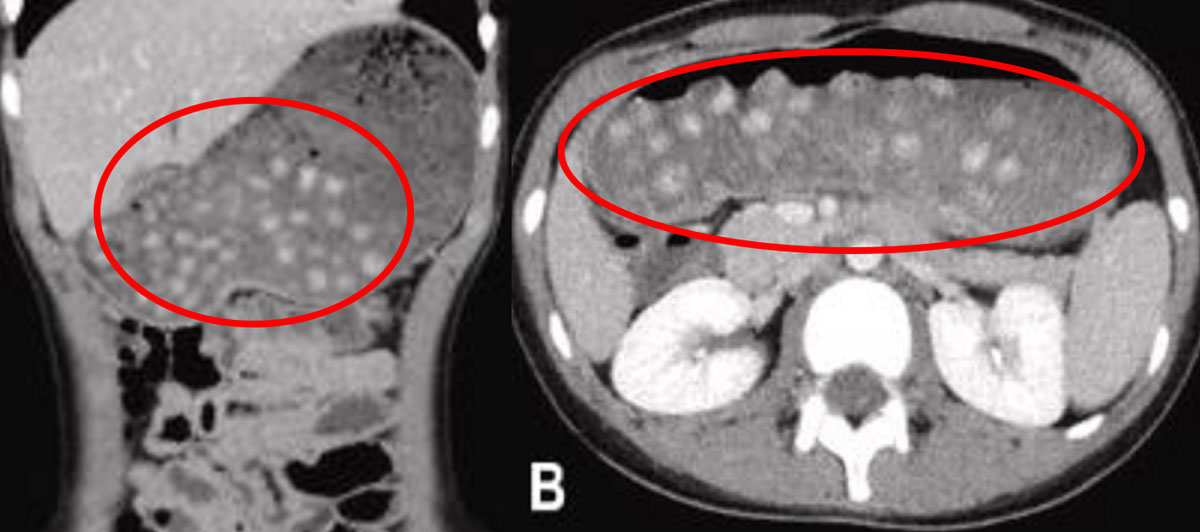

ÀϺ» ½ÃÁî¿ÀÄ«Çö ÈÄÁö½Ã Á¾ÇÕº´¿ø ¼Ò¾Æ°ú ÀÇ·áÁø¿¡ µû¸£¸é, ±âÀúÁúȯÀÌ ¾ø´Â 10¼¼ ¿µ¾Æ°¡ »óº¹ºÎ ÅëÁõÀ» È£¼ÒÇÏ¸ç ³»¿øÇß´Ù. º¹ºÎ CT °Ë»ç °á°ú, À§ ³»¿¡ ´Ù¼öÀÇ ÁøÁÖ ¸ð¾ç µ¢¾î¸®µéÀÌ °üÂûµÆ´Ù. Å©±â´Â 8~10mm Á¤µµ¿´´Ù.

±×´Â ³»¿ø 6½Ã°£ Àü ¹öºíƼ¸¦ ¼·ÃëÇß¾ú´Ù°í ÀüÇß°í, À§¸¦ ¸·°í ÀÖ´ø µ¢¾î¸®µéÀÇ Á¤Ã¼´Â ¹öºíƼ ¼Ó¿¡ µé¾î Àִ ŸÇÇ¿ÀÄ« ÆÞÀ̾ú´Ù. ÀÌ¿¡ ÀÇ·áÁøÀº ÄÚ·Î °¡´À´Ù¶õ °üÀ» ³Ö¾î À§ÀÇ ¾Ð·ÂÀ» ³·ÃçÁÖ´Â ºñÀ§°ü °¨¾Ð¼úÀ» ½ÃÇàÇß´Ù. ÀÌÈÄ ÃßÀû °üÂû °Ë»ç¿¡¼ À§ ³» º´º¯µéÀÌ ½ÊÀÌÁöÀåÀ¸·Î ¹èÃâµÈ µÚ ¼ÒÀåÀ¸·Î À̵¿ÇÑ °ÍÀÌ È®ÀεƴÙ.